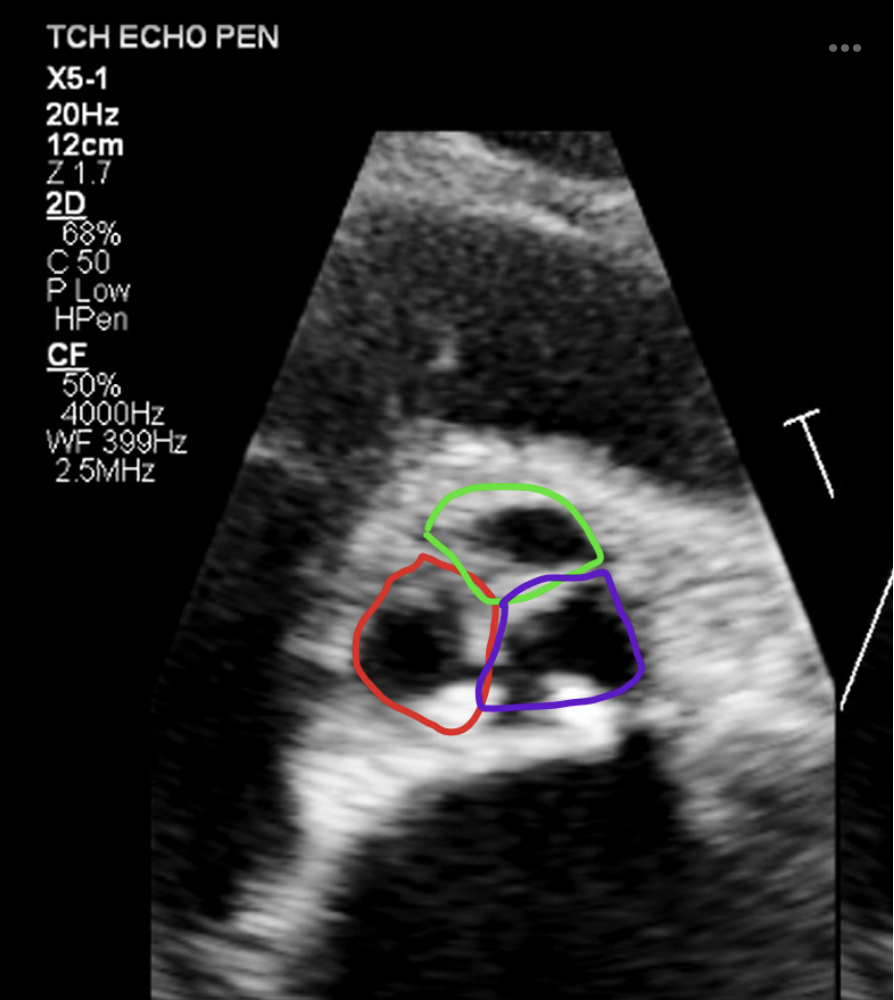

20

Q

What does this show and in what plane?

A

PSAX, Trileaflet AOV